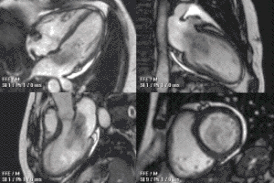

![]() Анимированное МРТ сердца демонстрирует большую миксому, пролабирующую из предсердия в желудочек и обратно через митральный клапан. | |

Дифференциальный диагноз включает другие опухоли сердца: липомы, рабдомиомы и (редко) тератомы. Эти опухоли сердца, как правило, не на ножке и чаще прорастают в сердечную мышцу. Применение магнитно-резонансной томографии (МРТ) может помочь неинвазивно диагностировать опухоль сердца. Однако, для верификации диагноза обычно требуется изучения образца ткани патогистологом.